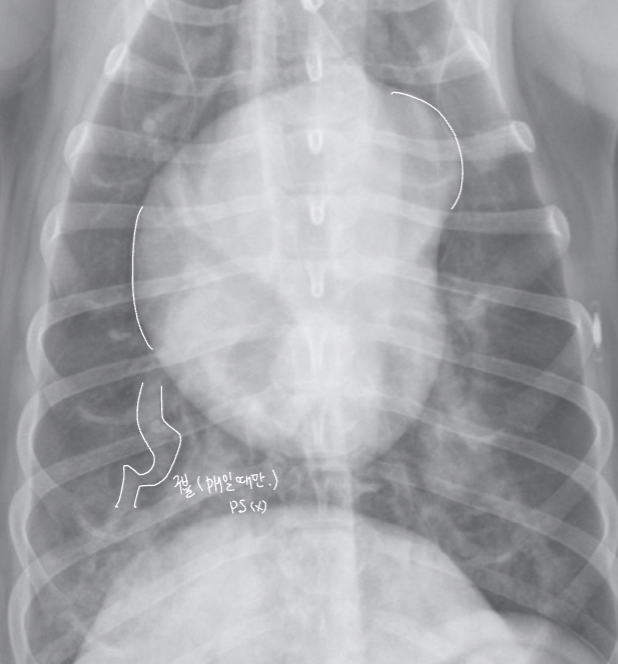

| Generalized cardiomegaly |

|---|

| RA, RV, LA, LV๊ฐ ๋ค ์ปค์ง โ Globoid heart |

| - Pericardial effusion - ์ฌํ ์์ชฝ ์ฌ์ฅ๋ณ (MVI + TVI) - PPDH (Peritoneopericardial diaphragmatic hernia) - Cardiomyopathy (DCM) - Anesthesia, bradycardia |

![]() |